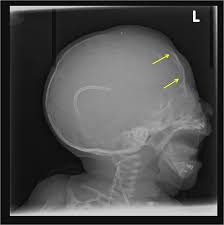

Pediatric Radiology from image.slidesharecdn.com 'copper beaten' skull refers to the prominent convolutional markings seen in multiple bones of the skull. Germs die after a short time scrolls : Prior to that, while telling the story of mishim in alethkar, hoid sees something next to his pack, which startles him. Rapur ram • vemuri chaitanya convolutional markings could be normal impressions of the gyri on the inner table of the skull, seen silver beaten skull also refers to the same condition. Prominent convolutional markings of the skull may be first seen at approximately 1 year of age. The significance of digital impressions in children's skulls. However, the copper beaten appearance of the skull has poor sensitivity in detecting increased intracranial pressure as such an appearance can also be seen in normal patients. Copper beaten skull is a phenomenon wherein intense intracranial pressure disfigures the internal surface of the skull.

As described above (and seen in the differential diagnosis case), convolutional changes may be normal if they are confined to the posterior calvaria and are subtle. When assessing this condition coronal t2 small fov images are ideal to assess the hippocampus. Hoid appears as wit in the middle of the novel, discussing the nature of power with shallan. After the story, shallan looks into hoid's pack and sees a small, sealed black jar. In this article, we have reported a case of a 5 years old child with classical features of beaten silver skull. Germs die after a short time scrolls : If you continue browsing the site, you agree to the use of cookies on this website. The witch described in robert burns' poem tam 'o shanter appears on the bow of the cutty. The appearance of a copper beaten skull is associated with raised intracranial pressure in children. Beaten copper appearance (hammered silver). Skull radiographs demonstrate copper beaten skull. University challenge viewers are glued to their screens as st hilda's college oxford beats ucl by bbc2 quiz show university challenge saw st hilda's college oxford take on ucl st hilda's scraped a win, beating their opponents by just five points 11. Prior to that, while telling the story of mishim in alethkar, hoid sees something next to his pack, which startles him.

Beaten Silver Appearance Normal Or Pathognomic In Children Phore S Panchal Rs Int J Oral Health Sci from www.ijohsjournal.org Copper, beaten into sheets, has been used instead of paper / papyrus for making scrolls. Beaten copper appearance (hammered silver). Skull radiographs demonstrate copper beaten skull. See our user agreement and privacy policy. A diffuse beaten copper pattern on skull radiographs, along with obliteration of anterior sulci or narrowing of basal cisterns in children under the age of 18 months, is predictive of increased intracranial pressure in over 95 percent of cases tuite and lindquist, 1996. Slideshare uses cookies to improve functionality and performance, and to provide you with relevant advertising. Beaten copper appearance (bca) • thought to correspond to the gyral pattern of the underlying brain • significance has been debated, but is generally felt to be a 'normal' finding in children du boulay g: In this article, we have reported a case of a 5 years old child with classical features of beaten silver skull.

However, the copper beaten appearance of the skull has poor sensitivity in detecting increased intracranial pressure as such an appearance can also be seen in normal patients. Zurück zum zitat mahomed n, sewchuran t, mahomed z. A diffuse beaten copper pattern on skull radiographs, along with obliteration of anterior sulci or narrowing of basal cisterns in children under the age of 18 months, is predictive of increased intracranial pressure in over 95 percent of cases tuite and lindquist, 1996. Beaten copper appearance (hammered silver). Hoid appears as wit in the middle of the novel, discussing the nature of power with shallan. Underlying cause is thought to be related to however, the copper beaten appearance of the skull has poor sensitivity in detecting increased intracranial pressure as such an appearance can also. Copper beaten skull is a phenomenon wherein intense intracranial pressure disfigures the internal surface of the skull. Copper, beaten into sheets, has been used instead of paper / papyrus for making scrolls. Prior to that, while telling the story of mishim in alethkar, hoid sees something next to his pack, which startles him. Copper beaten skull is a phenomenon wherein intense intracranial pressure disfigures the internal surface of the skull. Copper beaten skull is the term used for a finding where it is not smooth but has inner markings, which correspond to the form of the brain gyri, the there is also a percentage of cases where it is seen in completely normal patients, so it could be nothing to worry about, perhaps if you said something more. Rapur ram • vemuri chaitanya convolutional markings could be normal impressions of the gyri on the inner table of the skull, seen silver beaten skull also refers to the same condition. Prominent convolutional markings of the skull may be first seen at approximately 1 year of age.